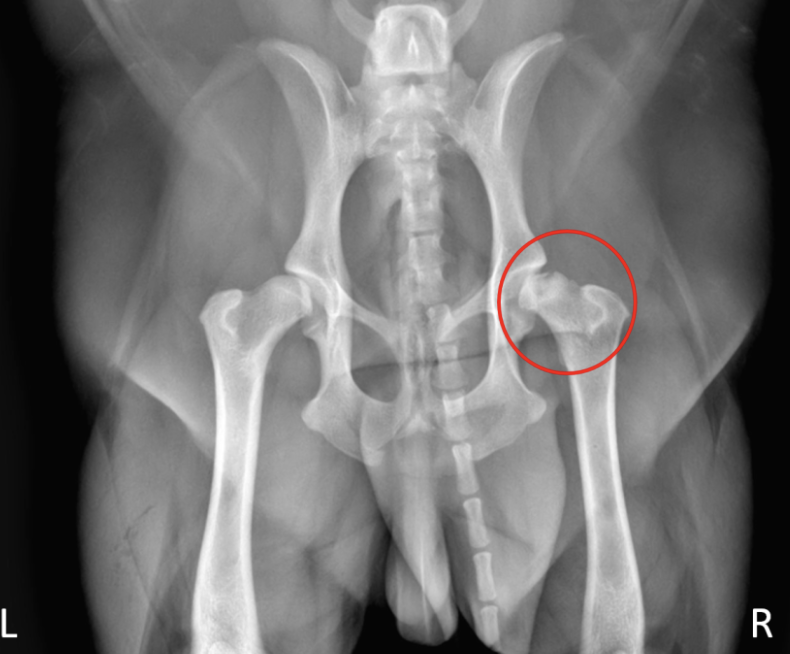

HD what does it look like of radiographs

Flattened femoral head

Thickened femoral neck

Shallow/ sclerotic acetabulum

Numerous osteophytes

What are some signs of arthritic changes

Acetabulum is almost not visible

Bone spurs above hip joints

Thickening and remodeling of the femoral head